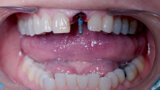

Fig. 13: Healing abutment to protect connection.